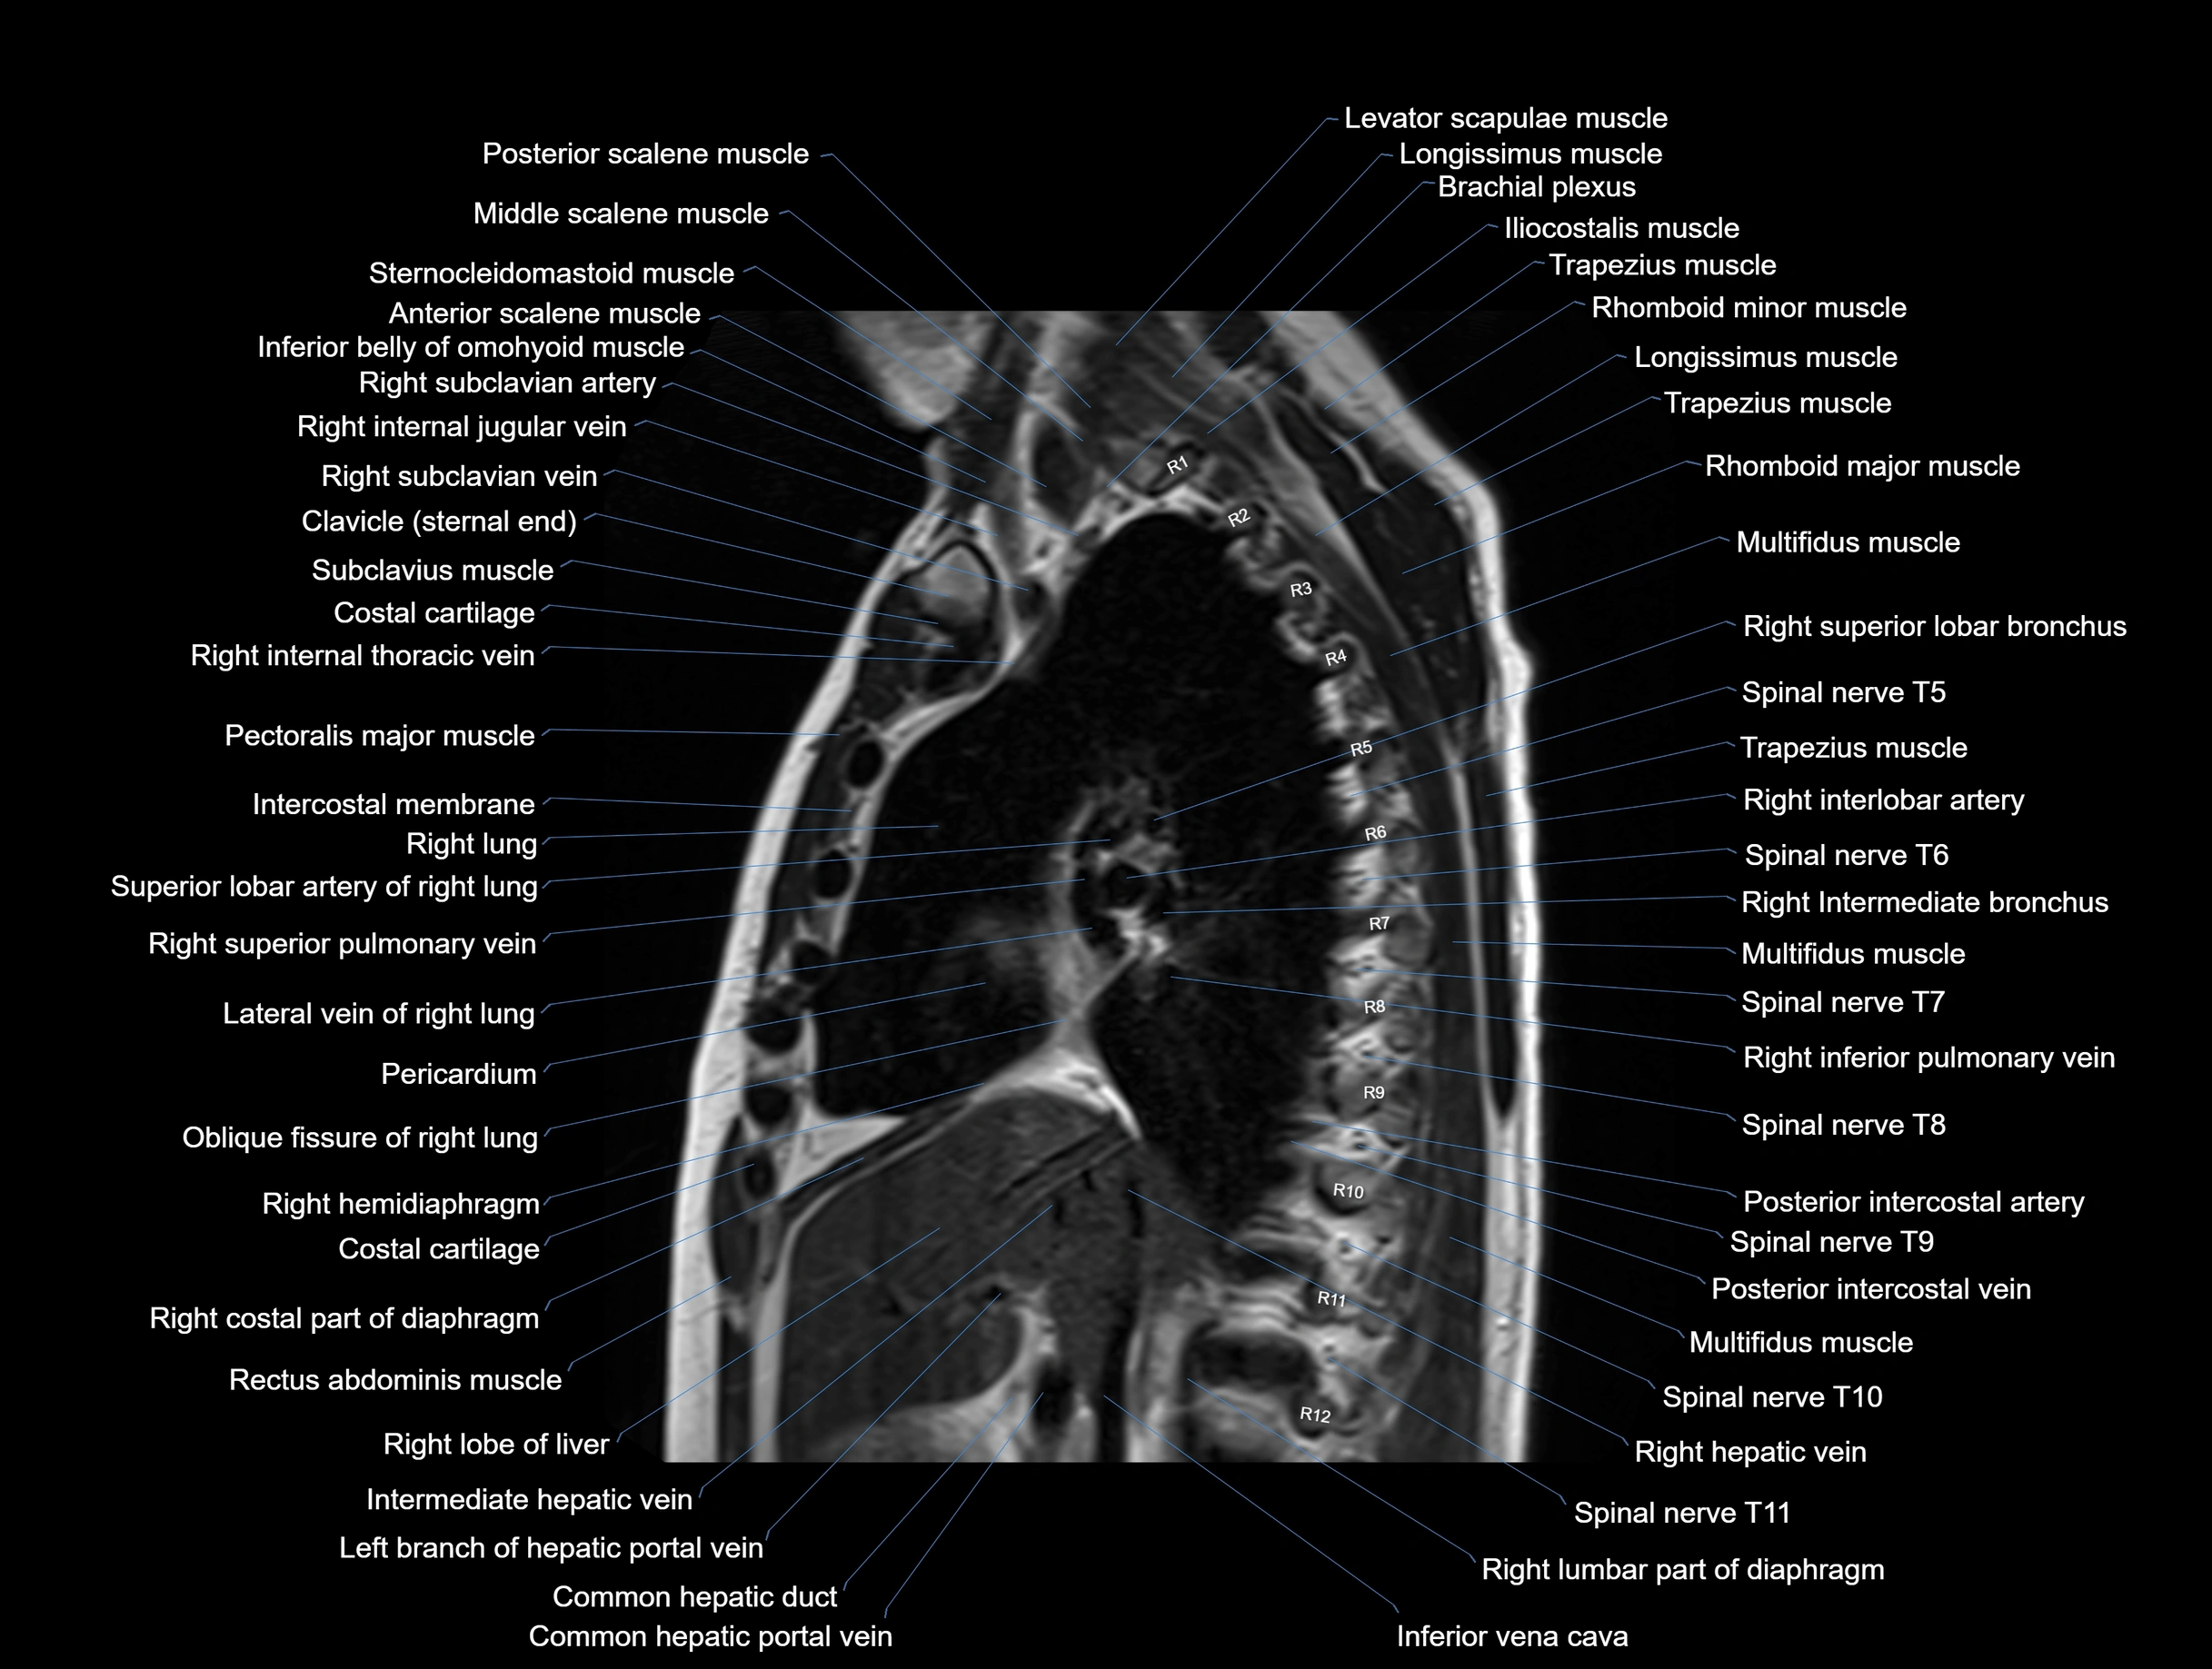

MRI images